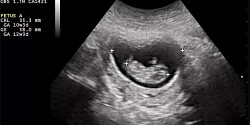

18 janvier 2023Étude en échocardiographie foetale - Dr Frédéric Dallaire et son équipe

16 décembre 2022Nouvelle publication en janvier 2023